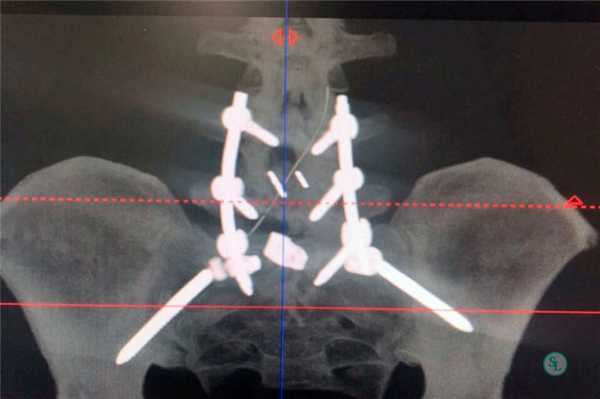

Индексы ASDAS, по-видимому, лучше, чем BASDAI, в связи с более строгой валидностью и высокой дискриминантной способностью. Индексы ASDAS «работают» при АС, ранних формах спондилоартропатий, рентгенонегативном осевом и периферическом АС. С помощью индексов ASAS определяются неактивная болезнь, умеренная, высокая и очень высокая активность заболевания при соответствующих им значениях индексов ASDAS (1,3, 2,1 и 3,5 единицы). Интервал изменения ≥ 1,1 единицы соответствует клинически значимому улучшению, а интервал ≥ 2,0 единиц — значительному улучшению [4]. По мнению экспертов, ASDAS не более 2,1 является целью лечения Т2Т [5]. Нами ниже предложен алгоритм лечения аксиального АС (рис. 1). Однако данные строгих клинических испытаний, способных доказать данную концепцию, пока отсутствуют. Актуальность этих поисков демонстрируют результаты неуклонного прогрессирования болезни, требующего хирургического вмешательства, которые представлены на рисунках 2 и 3.